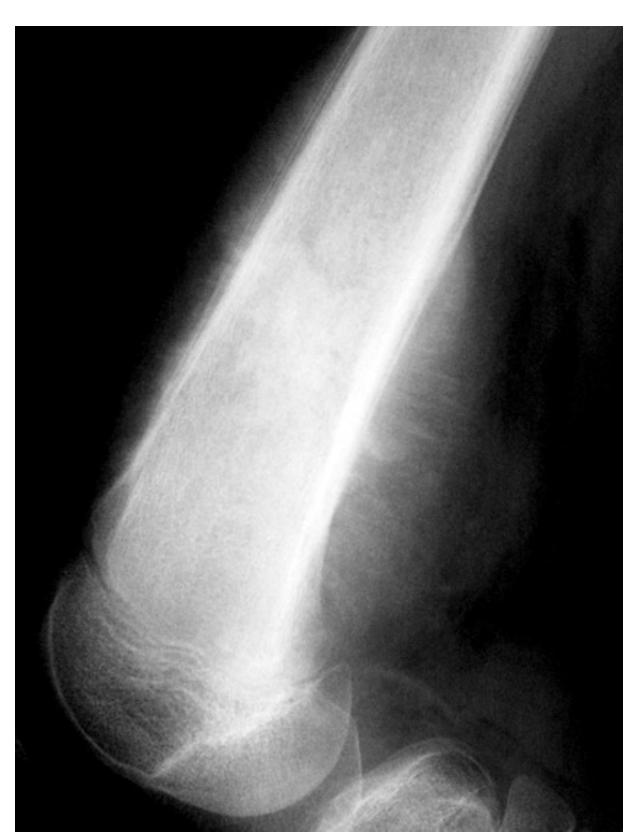

Monteggia Fracture

- Location: Proximal ulna fracture w/ radial head dislocation ย fracture of the proximal (or midโshaft) ulna with dislocation of the radial head at the elbow. ย